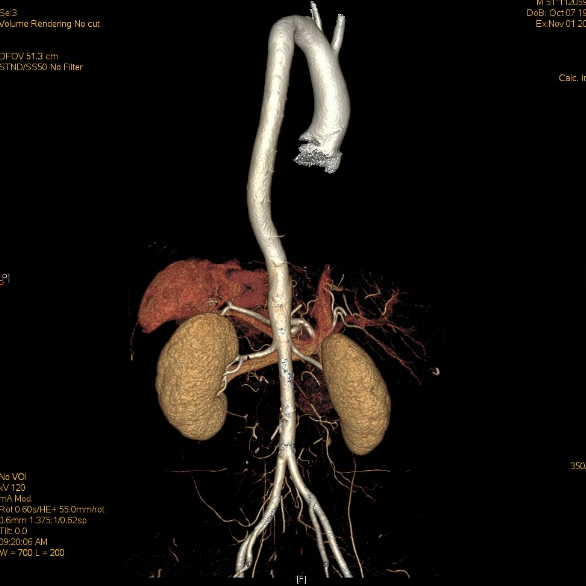

全主动脉+盆腔动脉增强CT

散在混合性斑块,管腔轻度狭窄;主动脉粥样硬化。